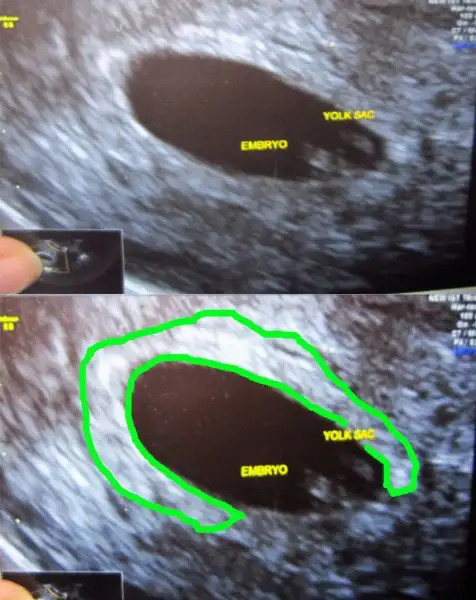

yabancı sitelere baktım canım. bebek ile plasenta daha 6 ya da 7 haftalıkken birbirinden uzak olabiliryormuş. bir kaç foto ekliyorum. bu ultrasonlar vajinal. ( bu arada bu bebişlerde plasenta yönü yani ramzi teorisi tutmuş)Cnm bu konuda bi karara varabilmemiz için burdaki plasentası sağda veya solda dediğimiz arkadaşlardan bi cvp gelmesi bizimde ona göre işe yarayıp yaramadıgını öğrenmemiz gerekiyo. Fakat çoğu daha cinsiyeti öğrenemedi galiba. Ben öğrenenlerin eski usglerine bakıorm bi kaç tane tuttu yani plasenta ve bebek solda oğlu olcakmş. Ama bi kaç tane tutması istisna olabilir canım. Ben hiçbi teoriye %100 doğru diyemem.

Evet canım bende okumuştum zaten bebekle plasentanın farklı yerlerde olduğunu biliyorum. Slvestr arkadaşımız bebek nerdeyse plasentada orda olur demişti. Ama öyle değil. Benim ilk gebeliğimde bariz bebek solda hatta en sola yapışık yani. Ama plasenta sağda ve benim 11 aylık bir cimcimem var. Yani plasenta olayı ilk gebeliğimde tuttu. Şimdi bebekte plasentada solda bakalım sonuç ne olacak. Eğer yine kızım olursa plasenta olayı yalan arkadaşlar. Tutanlar tesadüf dicez napalımyabancı sitelere baktım canım. bebek ile plasenta daha 6 ya da 7 haftalıkken birbirinden uzak olabiliryormuş. bir kaç foto ekliyorum. bu ultrasonlar vajinal. ( bu arada bu bebişlerde plasenta yönü yani ramzi teorisi tutmuş)

yabancı sitelere baktım canım. bebek ile plasenta daha 6 ya da 7 haftalıkken birbirinden uzak olabiliryormuş. bir kaç foto ekliyorum. bu ultrasonlar vajinal. ( bu arada bu bebişlerde plasenta yönü yani ramzi teorisi tutmuş)

Canım bu vajinal ultrason ve bebek sağda, teoriye göre erkek, demek ki sen de tutmuyor..Kızlar kızımın ultrasonu buldum diğer konularda kaydetmisim,resim atiyorumm bundada plasenta solda gibi geldi bana